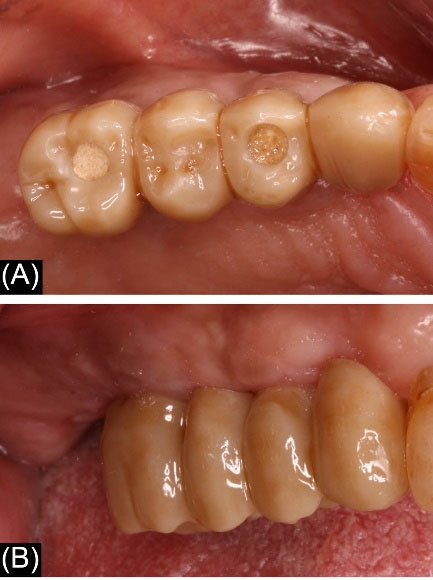

Figure 5. Clinical presentation of the Implant-supported zirconia fixed partial dentures (A) Occlusal view (B) Buccal view

joddd-16-258-g006